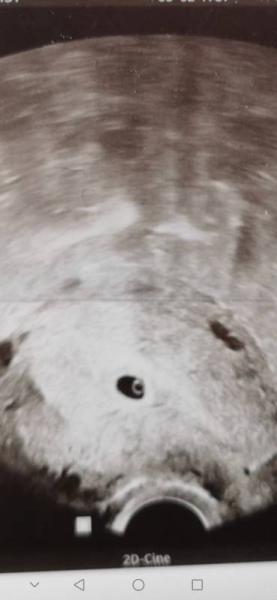

Sie hat jedoch ein Ultraschall gemacht und man konnte tatsächlich schon die fruchthöhle und den Dottersack sehen

Ich war gestern das erste mal beim Frauenarzt (5+5) Man hat den kleinen Wurm tatsächlich schon gesehn und muss daher erst am 21.03. wieder zur Untersuchung. Anbei häng ich auch mal ein Bild. Es ist schon faszinierend wie unterschiedlich dann doch die Frauenkörper sind, bzw. Wie viel dann doch 5 Tage ausmachen können. Ich drück die Daumen das man beim nächsten Termin mehr als den Dottersack sehen kann.

Dachte erst der erste Termin bei 5+5 wäre früh. Aber sie konnte die Schwangerschaft bestätigen, eine Eileiterschwangerschaft ausschließen und man konnte den Fötus schon erkennen.

Ich hatte heute an 6+3 den ersten Termin. Leider hat sich kein Embryo gezeigt :( ich hatte so auf einen Herzschlag gehofft. Die Ärztin war im Gegensatz zu mir ganz zufrieden mit dem Bild. Fruchthöhle und Dottersack sind gut. Naja. Nun gibt es den nächsten Termin in 9 Tagen. Dann sehen wir weiter.